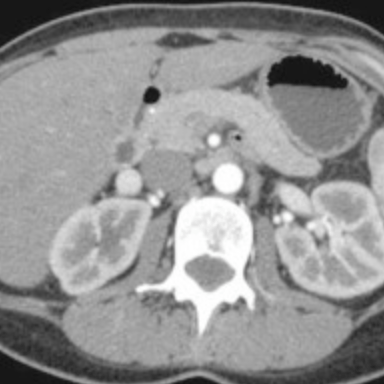

췌장의 몸통과 꼬리 부위가 하나의 영상절편에 놓여진 CT 횡단면영상입니다. 췌장의 꼬리는 언제나 예외없이 뒤쪽에 왼쪽 콩팥이 위치해있으며, 측면에는 비장이 존재합니다. 대부분은 비장의 아래쪽 부위가 췌장꼬리와 닿아있으며 20-30%정도에서는 좀 더 위쪽으로 올라와 비장의 hilum쪽과 닿아있지만, 초음파영상에서는 앞쪽에 존재하는 장관내공기음영에 가려져서 확인하기가 어렵습니다.